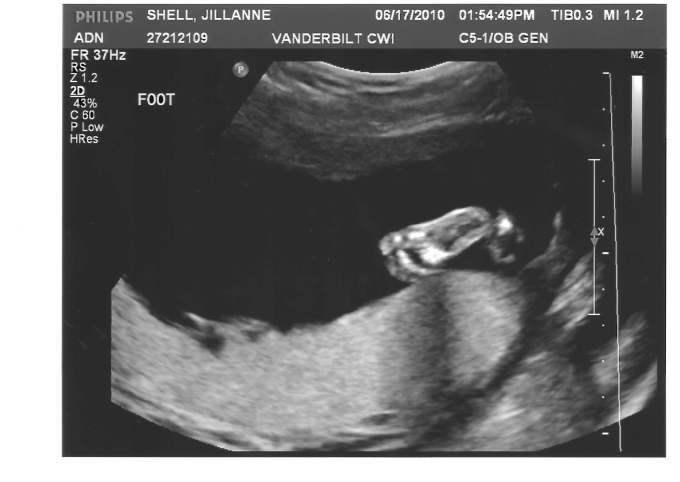

Nineteen weeks.

After my grandmother’s dream and my wife’s co-worker’s psychic’s prediction of it being a girl, it was pretty obvious to us what the gender of our baby would be.  I drove down to the appointment yesterday full of excitement, knowing that I could finally tell everyone that our intuition was correct once I would get the official confirmation.

Several anxious moments passed as the nurse showed us pictures our  our baby, then finally she asked us, “Do you want to know what it is?”

Laughing, full of confidence, we told her that we were quite sure already, but yes, tell us for sure.

“You’re having a boy.”

I wish I had a YouTube clip of our reaction.  “WHAT?!  NO WAY!  ARE YOU SERIOUS?!”  Etc., etc.  All exclaimed while hysterically laughing.

Not that it mattered either way to us.  I just don’t think I’ve ever been more surprised in my life.  I wish there was a way to type in a “laughing font” to better show my tone here.  I’m so happy!  We’re having a boy!